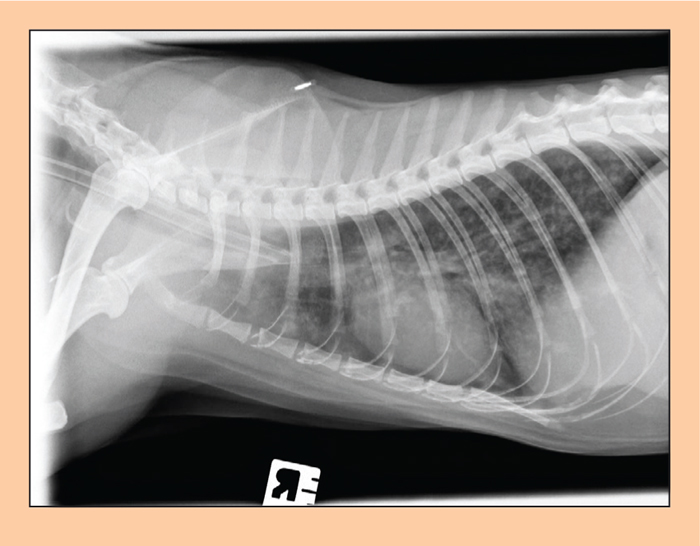

From messoffeelings.blogspot.com

Lungworm In Cats X Ray Can Cats Get Lung Infections A variety of viruses, bacteria, fungi, and. Feline upper respiratory infection is a common illness in cats. How to treat feline upper respiratory illness. Most upper respiratory infections in cats will resolve themselves with a little extra tlc and time. It’s similar to a cold, but it can be much more serious. Upper respiratory infections (uris) are one of the. Can Cats Get Lung Infections.